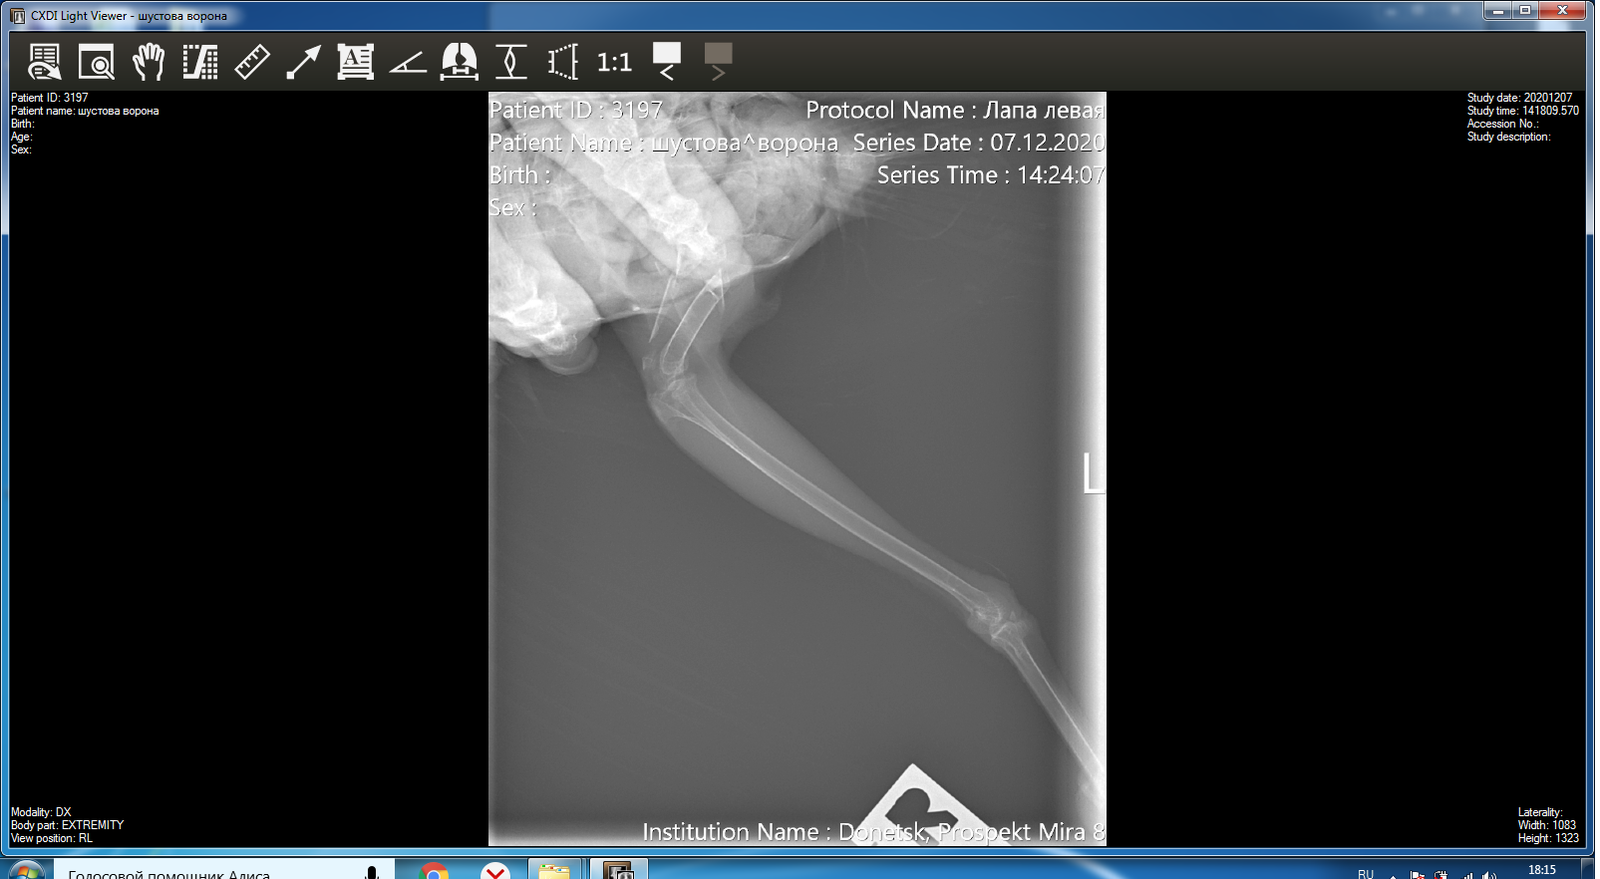

Открытый перелом плечевой кости у Грача

Открытый перелом плечевой кости" и "перелом лапы в бедре"(закрытый или открытый тоже?), также что у него "истощение по килю"

Не хирург и не консультант, но, мне кажется, перелом свежий и тогда нужно анатомически правильно сложить и зафиксировать места переломов. Оба перелома в неудобных для фиксации местах, так что повязку сложно закрепить. Если бы был газовый наркоз (наиболее безопасный для птиц) и специалист по птицам, тогда можно было бы поставить спицы. Если такой возможности нет, то попробовал бы закрепить лапу, вправить кости (возможно, сперва откусить кусачками острые края кости, предварительно местно пшикнув Лидокаин), примотать крыло к туловищу самоклеящимся бинтом или малярным скотчем, но не туго, чтобы птица могла нормально дышать (смотреть по состоянию и самочувствию птицы, комфортно ли ей, не дышит ли постоянно тяжело) и был доступ к ранам для обработки. Это нужно максимально быстро - кости у птиц срастаются быстро. В крайнем случае, птицы живут и с такими травмами (но острые края обкусайте).

@fishka операцию делать нельзя, у птицы крайнее истощение по килю + 2 перелома, не переживёт.

Фото зоны перелома, четкое. Перо вокруг окна состричь, вообще все перо вокруг, мешающее обзору и чистоте окна перелома.